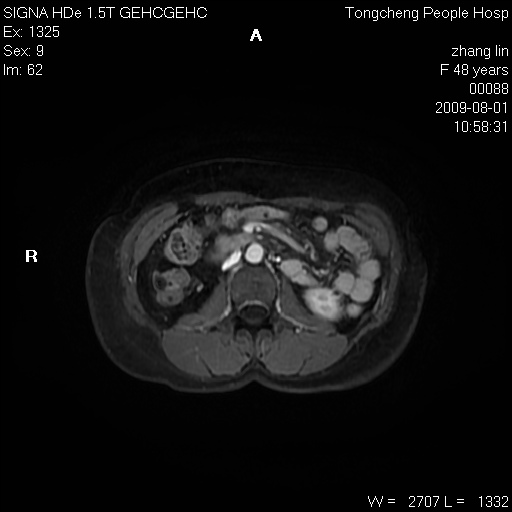

女,48岁。健康体检,彩超发现右肾占位性病变。平素健康。

临床诊断:右肾占位性病变,性质待定(囊肿?肿瘤?)。

上中腹部mr平扫+增强扫描,图像如下:

右肾上极见一类圆形病灶,t1wi呈等信号t2wi呈等高混杂信号,三期增强无强化,边界清---考虑囊肿出血。

同反相位均表现为等信号,病变无强化,考虑含蛋白的囊肿可能,弥散加权相或许有些帮助,